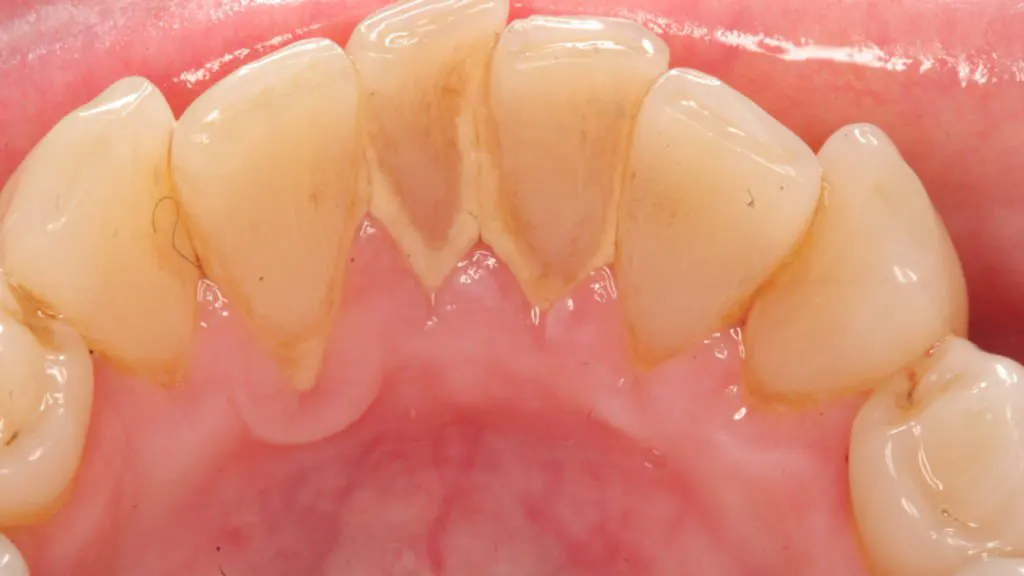

Sử dụng dụng cụ tự lấy vôi răng tại nhà được các chuyên gia khuyên không nên dùng. Với trường hợp, vôi răng chưa cứng và chưa xuất hiện nhiều có thể sử dụng các dụng cụ tự lấy cao răng. Tuy nhiên, vôi răng xuất hiện dày đặc, người bệnh cần đến nha khoa để bác sĩ thực hiện lấy cao răng. Khi vôi răng xuất hiện nhiều, người bệnh sử dụng các dụng cụ tự lấy vôi răng có thể khiến răng bị tổn thương, chảy máu chân răng, viêm nướu, nhiễm trùng, viêm nha chu và mòn men răng.